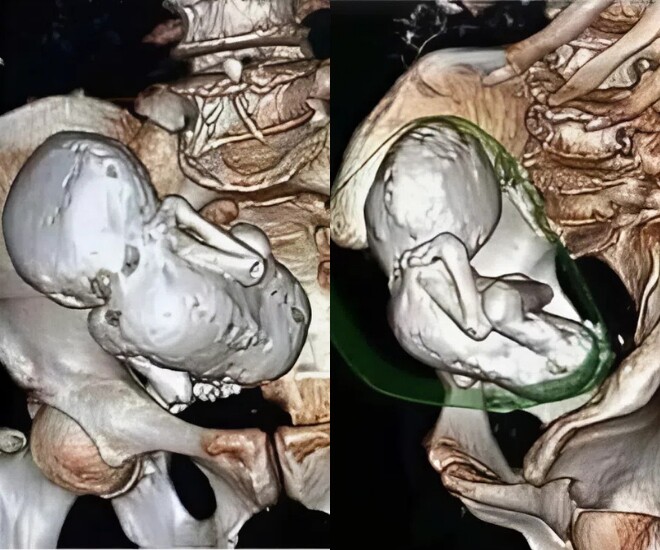

Ban đầu, cụ bà 73 tuổi nhập viện để kiểm tra sức khỏe định kỳ. Tuy nhiên, sau khi tiến hành chụp CT, các bác sĩ đã phải sững sờ khi phát hiện một khối bất thường trong bụng. Quan sát kỹ, họ nhận ra đây không phải khối u, mà chính là một thai nhi đã chết lưu và vôi hóa suốt 3 thập kỷ.

Trường hợp hiếm hoi này nhanh chóng lan truyền trên mạng xã hội sau khi một tài khoản với 4,8 triệu lượt theo dõi đăng tải hình ảnh cùng chú thích: “Đây là bào thai bị vôi hóa tồn tại 30 năm trong cơ thể một phụ nữ 73 tuổi".

Phim chụp CT cho thấy thai nhi "hoá đá" trong bụng cụ bà 73 tuổi.